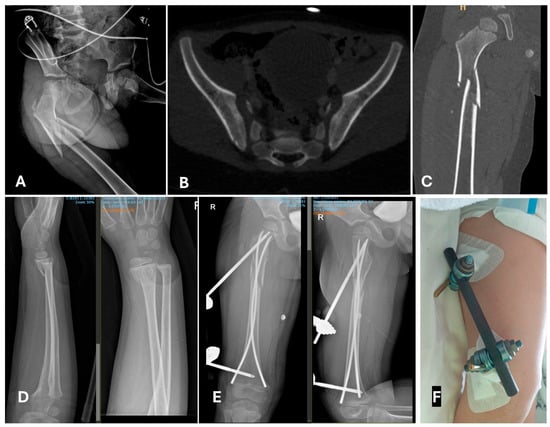

4.2. Is a Temporary Damage Control Surgery (DCO) Indicated?

4.3. Does the PPT/PMT Patient Need a Different Treatment Method Because of His/Her General Conditions?